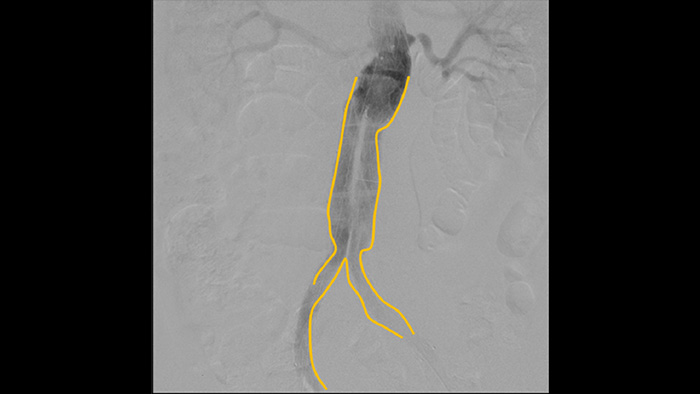

Use the Outlining tool to easily mark a bifurcation or side branches by simply drawing on the monitor of the Mobile Viewing Station with your finger or an externally connected mouse.

Enhance visibility of tortuous vasculature with Iodine and CO2 contrast medium options. Easily control injections at table side. For patients with renal failure, you can use the CO2 option to easily visualise small vessels without using iodine contrast.